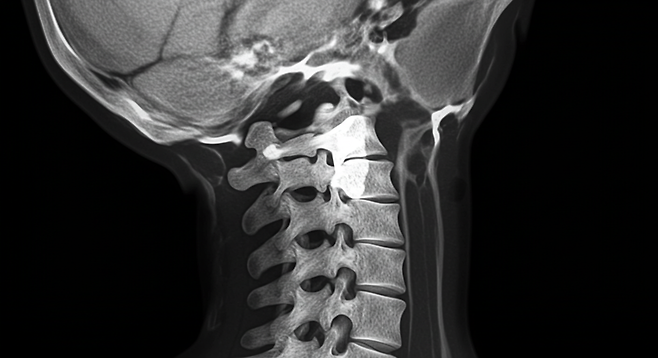

이 병은 척추를 지탱하는 인대가 뼈처럼 굳어지면서 신경을 누르고, 심하면 신체 마비까지 초래하는 심각한 질환입니다.

후종인대골화증은 척추를 지지하는 인대, 특히 후종인대가 뼈처럼 단단해지며 두꺼워지는 질환입니다.

인대가 굳어지면 척추 신경이 눌려 손·팔 저림, 감각 저하, 근력 저하, 보행 장애, 심하면 사지마비나 배뇨·배변 장애까지 초래할 수 있습니다.

진단은 방사선 촬영, CT, MRI 등으로 인대의 뼈화와 척수 압박 정도를 확인합니다.